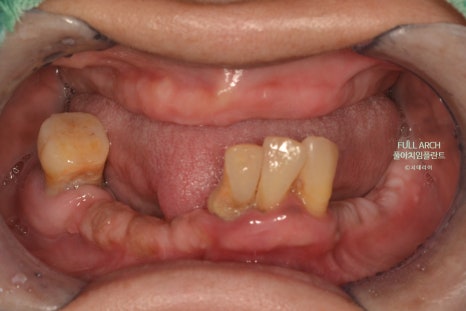

풀아치가 적합한 경우로는 다양한 복합적 치료가 불가능 하여 아래의 징후를 예를 들 수 있다.

광범위한 충치

잇몸질환으로 축적된 염증과 반복되는 감염으로 잇몸뼈를 상실한 경우

잇몸 퇴축으로 임플란트가 불가능한 경우

틀니사용이 불편한 경우

빠지거나 깨진치아가 여러개로 복합적인 문제들로 치료의 한계가 있는 경우